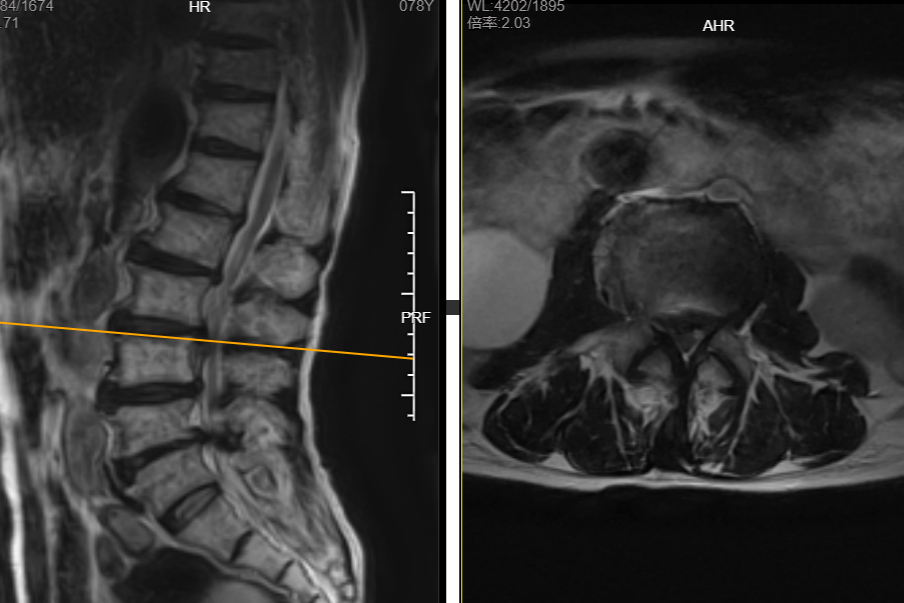

接诊的浙大邵逸夫医院绍兴院区骨科蒋超副主任医师表示,肌力归零意味着神经严重受损,必须尽快干预,否则可能永久丧失功能。老人家在外院做的核磁提示腰椎多节段病变,椎管重度狭窄,病情是比较复杂的,而且大爷是高龄患者,如果贸然开刀,手术风险极高。

“医生,我看报告上写着好多节腰椎存在问题,是不是全坏了,都要处理吗?”面对患者和家属的担心,骨科医疗团队没有急于手术,而是启动“精准诊疗程序”,结合患者的症状、体征,以及腰椎影像学检查,分析患者短时间内出现下肢疼痛无力的原因。

“多节腰椎突出不等于每节都是‘罪犯’。”蒋医师解释,“你爸爸年纪大,基础毛病较多,盲目处理所有病变不仅创伤大,还可能破坏脊柱稳定性。并且这个年龄不一定能吃得消做大手术。所以精准揪出‘责任节段’,是治疗成败的核心。”

经科室内讨论后,最终锁定责任节段为腰椎3/4的急性椎间盘突出,而其他几节病变暂时不需要处理。